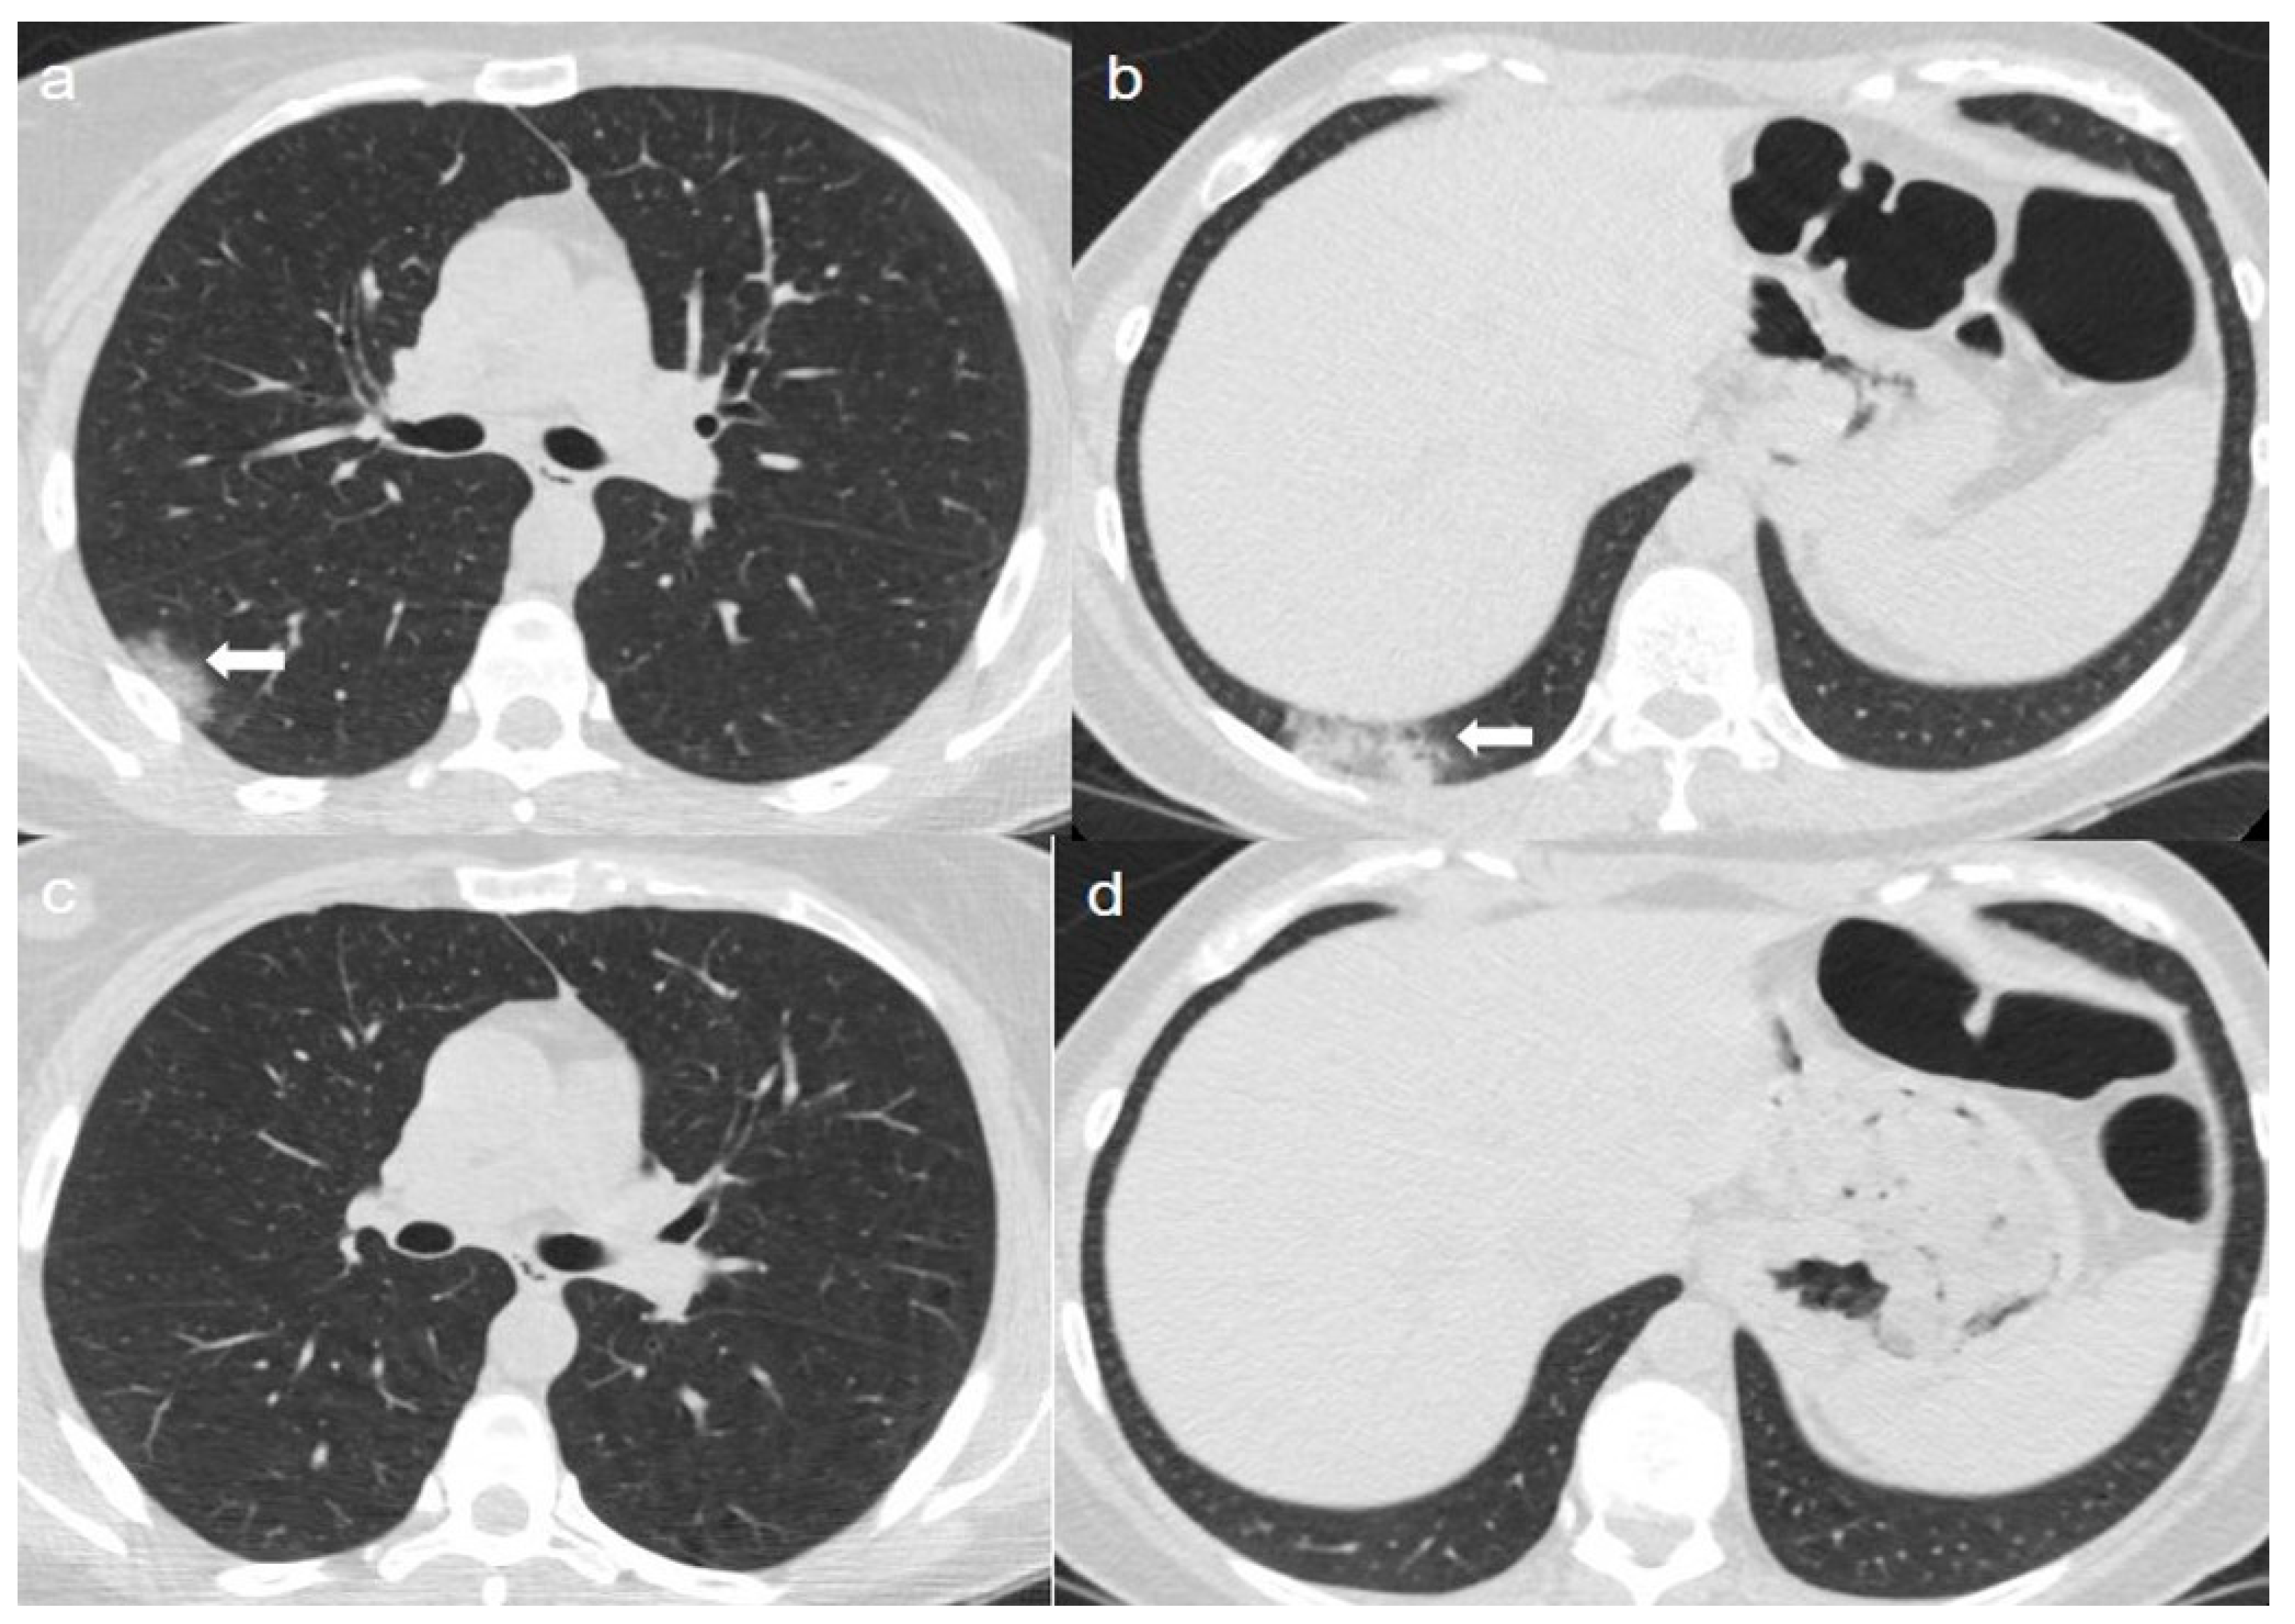

On admission, an unenhanced chest CT showed multiple, rounded ground-glass opacities (GGOs) with peripheral distribution, especially in the right lower lobe (Figure 1a,b).

(a,b) CT shows areas of ground-glass opacities (GGO) with peripheral distribution in right lower lobe (arrows). (c,d) CT after 4 months from the onset of symptoms shows complete reabsorption of GGOs with no lung abnormalities.

A chest CT at 4 months from the onset of symptoms showed complete reabsorption of GGOs with no lung abnormalities (Figure 1c,d).